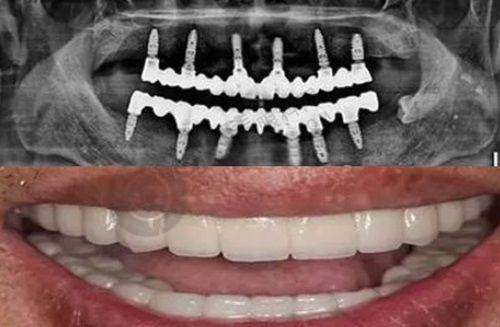

在了解福州美可普口腔预约方式之前,先为大家介绍一下相关的口腔项目信息。此次涉及的口腔项目为口腔外科,参考金额约为300元,预计修复时间大概是90天。福州美可普口腔凭借其广泛的布局和专精的医疗团队,在福建省口腔医疗领域占据着重要地位。它的各个分院分布在不同城区,方便周边居民就诊。而本文的目的就是要让大家清楚地知道如何通过多种方式预约福州美可普口腔的诊疗服务。除了下面要介绍的具体预约方式外,大家还可以通过该平台进行预约。只需向客服留下个人需求和联系方式,之后等待客服发送预约成功的信息即可。